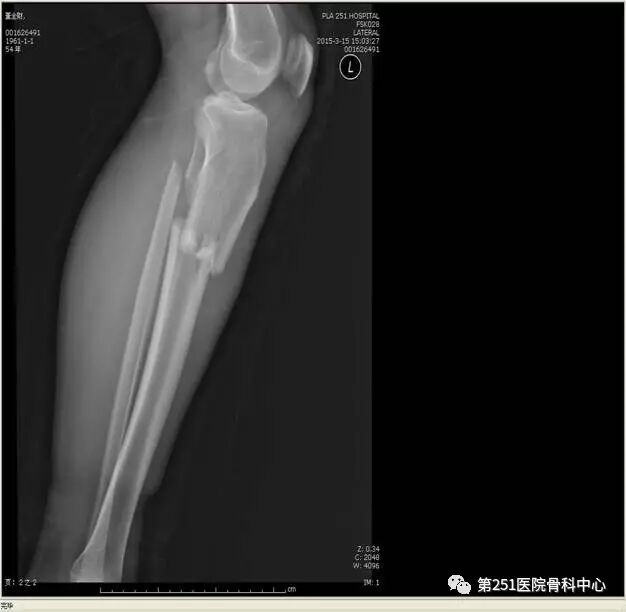

病例4:女性,车祸伤,同侧股骨、股骨颈合并胫腓骨骨折。

![]()